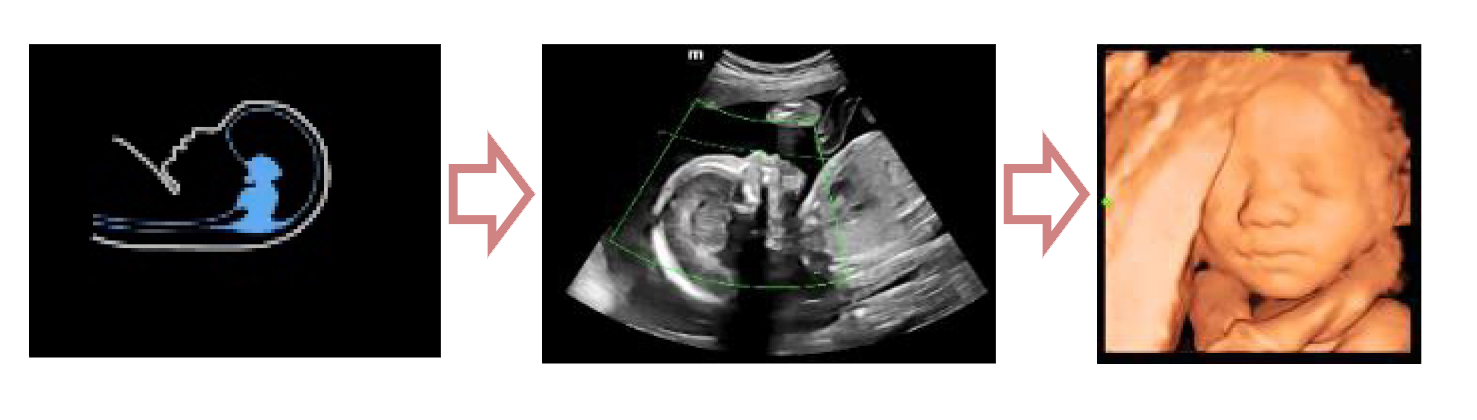

С легкостью получайте потрясающие объемные изображения лица плода.

- Автоматическое распознавание лица плода

- Автоматическая подстройка зоны интереса и положения до оптимального

- Автоматический определение параметров рендеринга лица плода